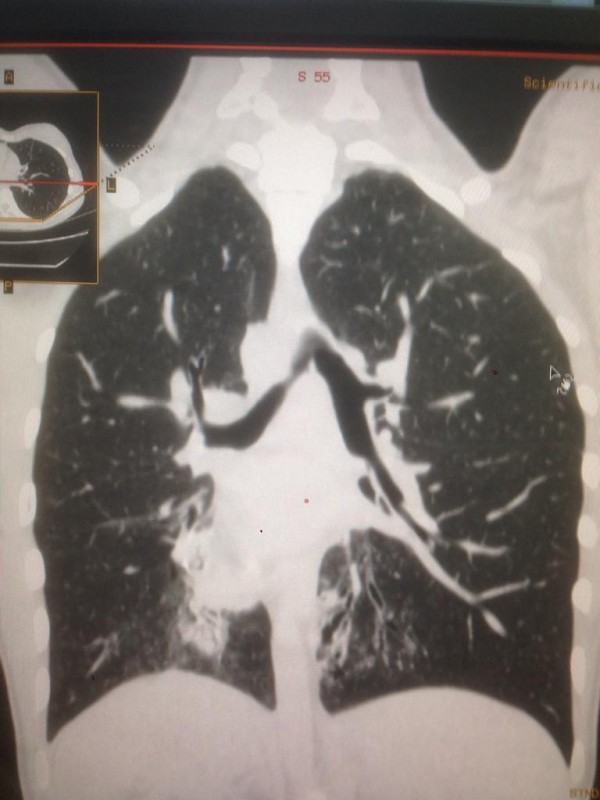

Синдром Зиверта-Картагенера. Снимок предоставлен Сундетом Саргеловым

Также зеркальное расположение внутренних органов встречается при синдроме Зиверта-Картагенера, это аутосомно-рецессивное генетическое заболевание. Его коэффициент один случай из 50 тысяч человек. В настоящее время в Казахстане на учете с такой патологией состоят 16 детей.

"Это генное нарушение. При нем у людей нездоровы дыхательные пути. Характерные черты: синклиты, бронхоэктазы и зеркальное расположение органов. Люди с таким диагнозом испытывают слабость, температуру, боль в ушах, одышку, хрипы. Поэтому пациенты с раннего возраста проходят лечение. Состоят на диспансерном учете у детского пульмонолога. В год они получают около пяти раз стационарное лечение, находятся под наблюдением врачей, пропивают антибиотики", - говорит собеседник.